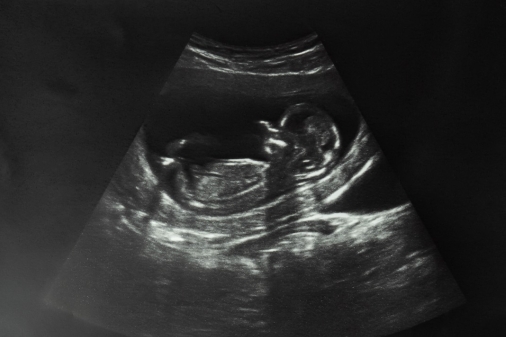

(CP) Siding with Planned Parenthood and other abortion providers in Ohio, a judge has expanded an earlier order blocking enforcement of a law that would ban most abortions after about six weeks into a pregnancy, or around the time a baby's heartbeat can be detected.

The law bans most abortions after a baby's heartbeat can be detected.